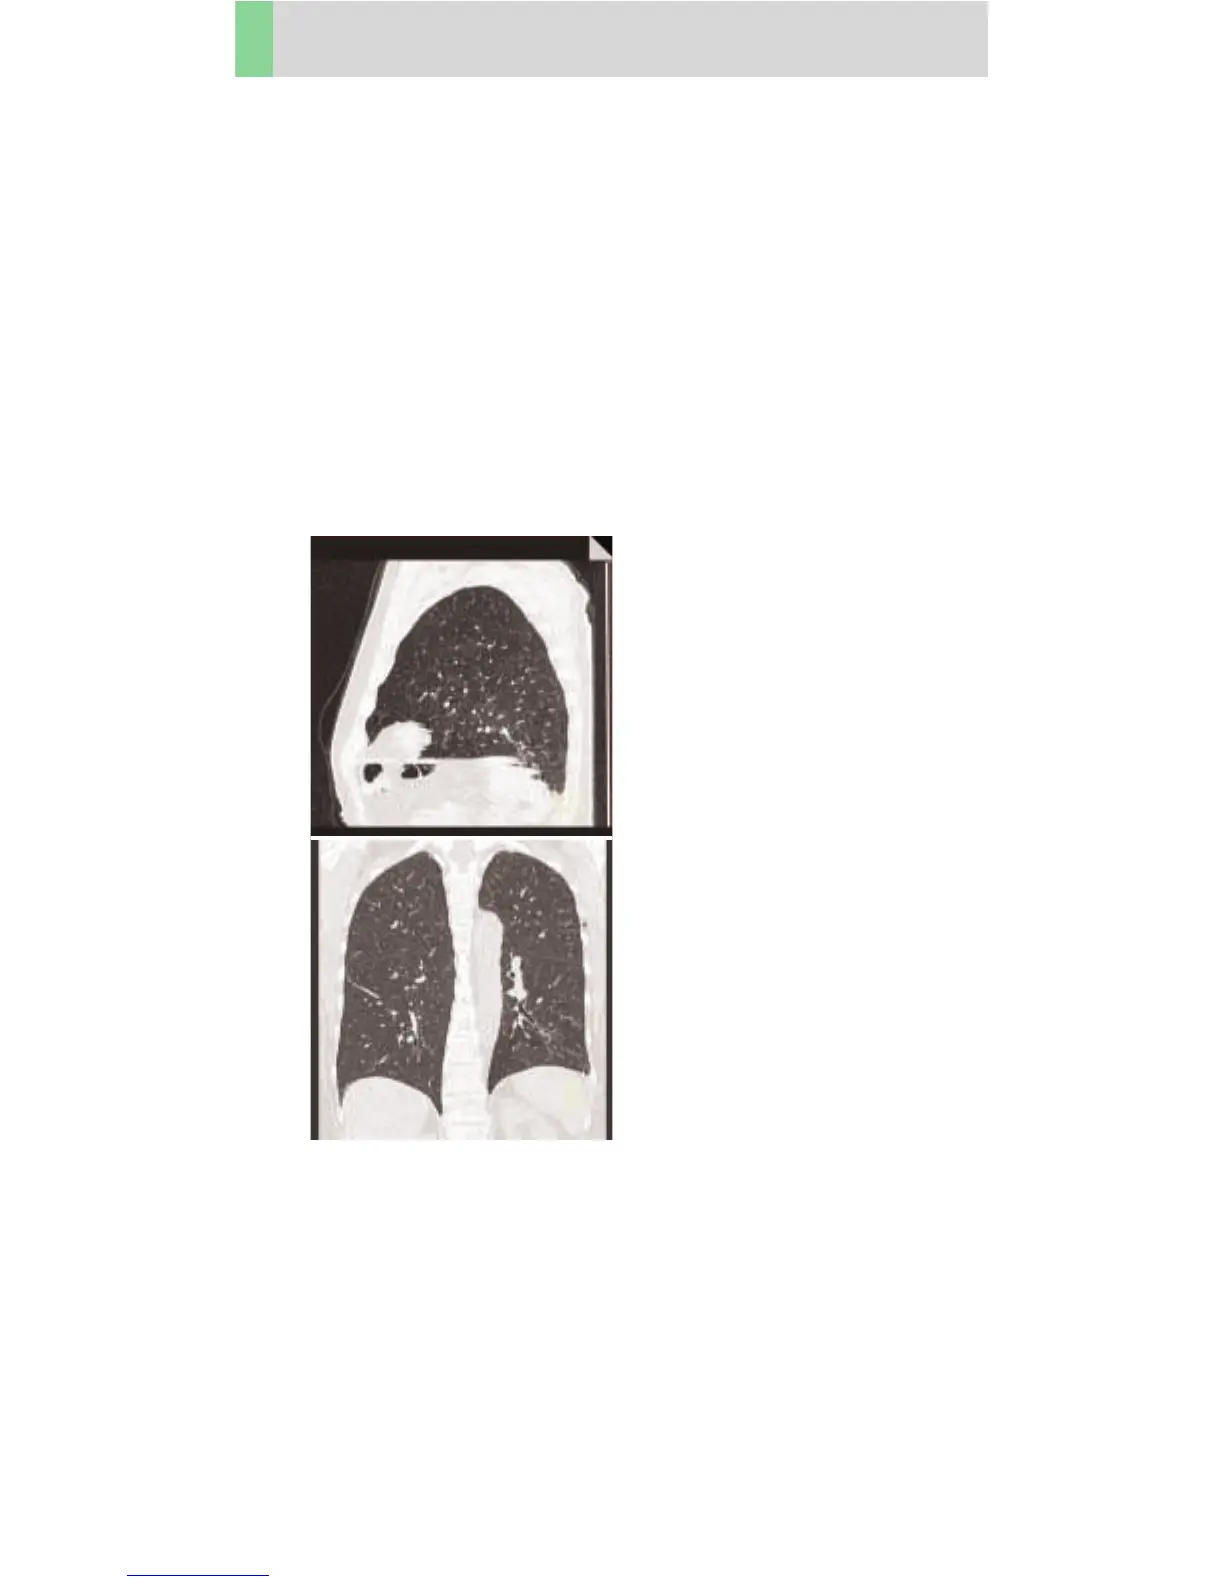

Thorax

ThoraxHR

Indications:

Spiral mode for HiRes studies, e.g. interstitial changes

in the lungs. Two recon jobs are predefined: thinner

slice reconstruction used for postprocessing, and thicker

slice reconstruction for soft tissue.

A range of 28 cm for the complete thorax will be

covered in 26.5 sec.